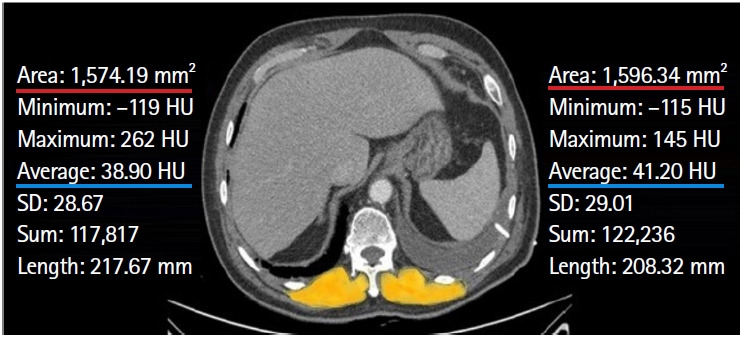

Methods: This single-center, retrospective, observational study analyzed elderly patients (≥65 years) with CAP hospitalized through an emergency department between March 2020 and December 2022. We collected their baseline characteristics and laboratory data at the time of admission. The paraspinal muscle index and attenuation were calculated at the level of the 12th thoracic vertebra using chest computed tomography taken within 48 hours before or after admission. Univariable and multivariable logistic regression analyses were conducted to evaluate the association between paraspinal muscle measurements and 28-day mortality. Receiver operating characteristic (ROC) curve and area under the curve (AUC) analyses were used to evaluate the prognostic predictive power.